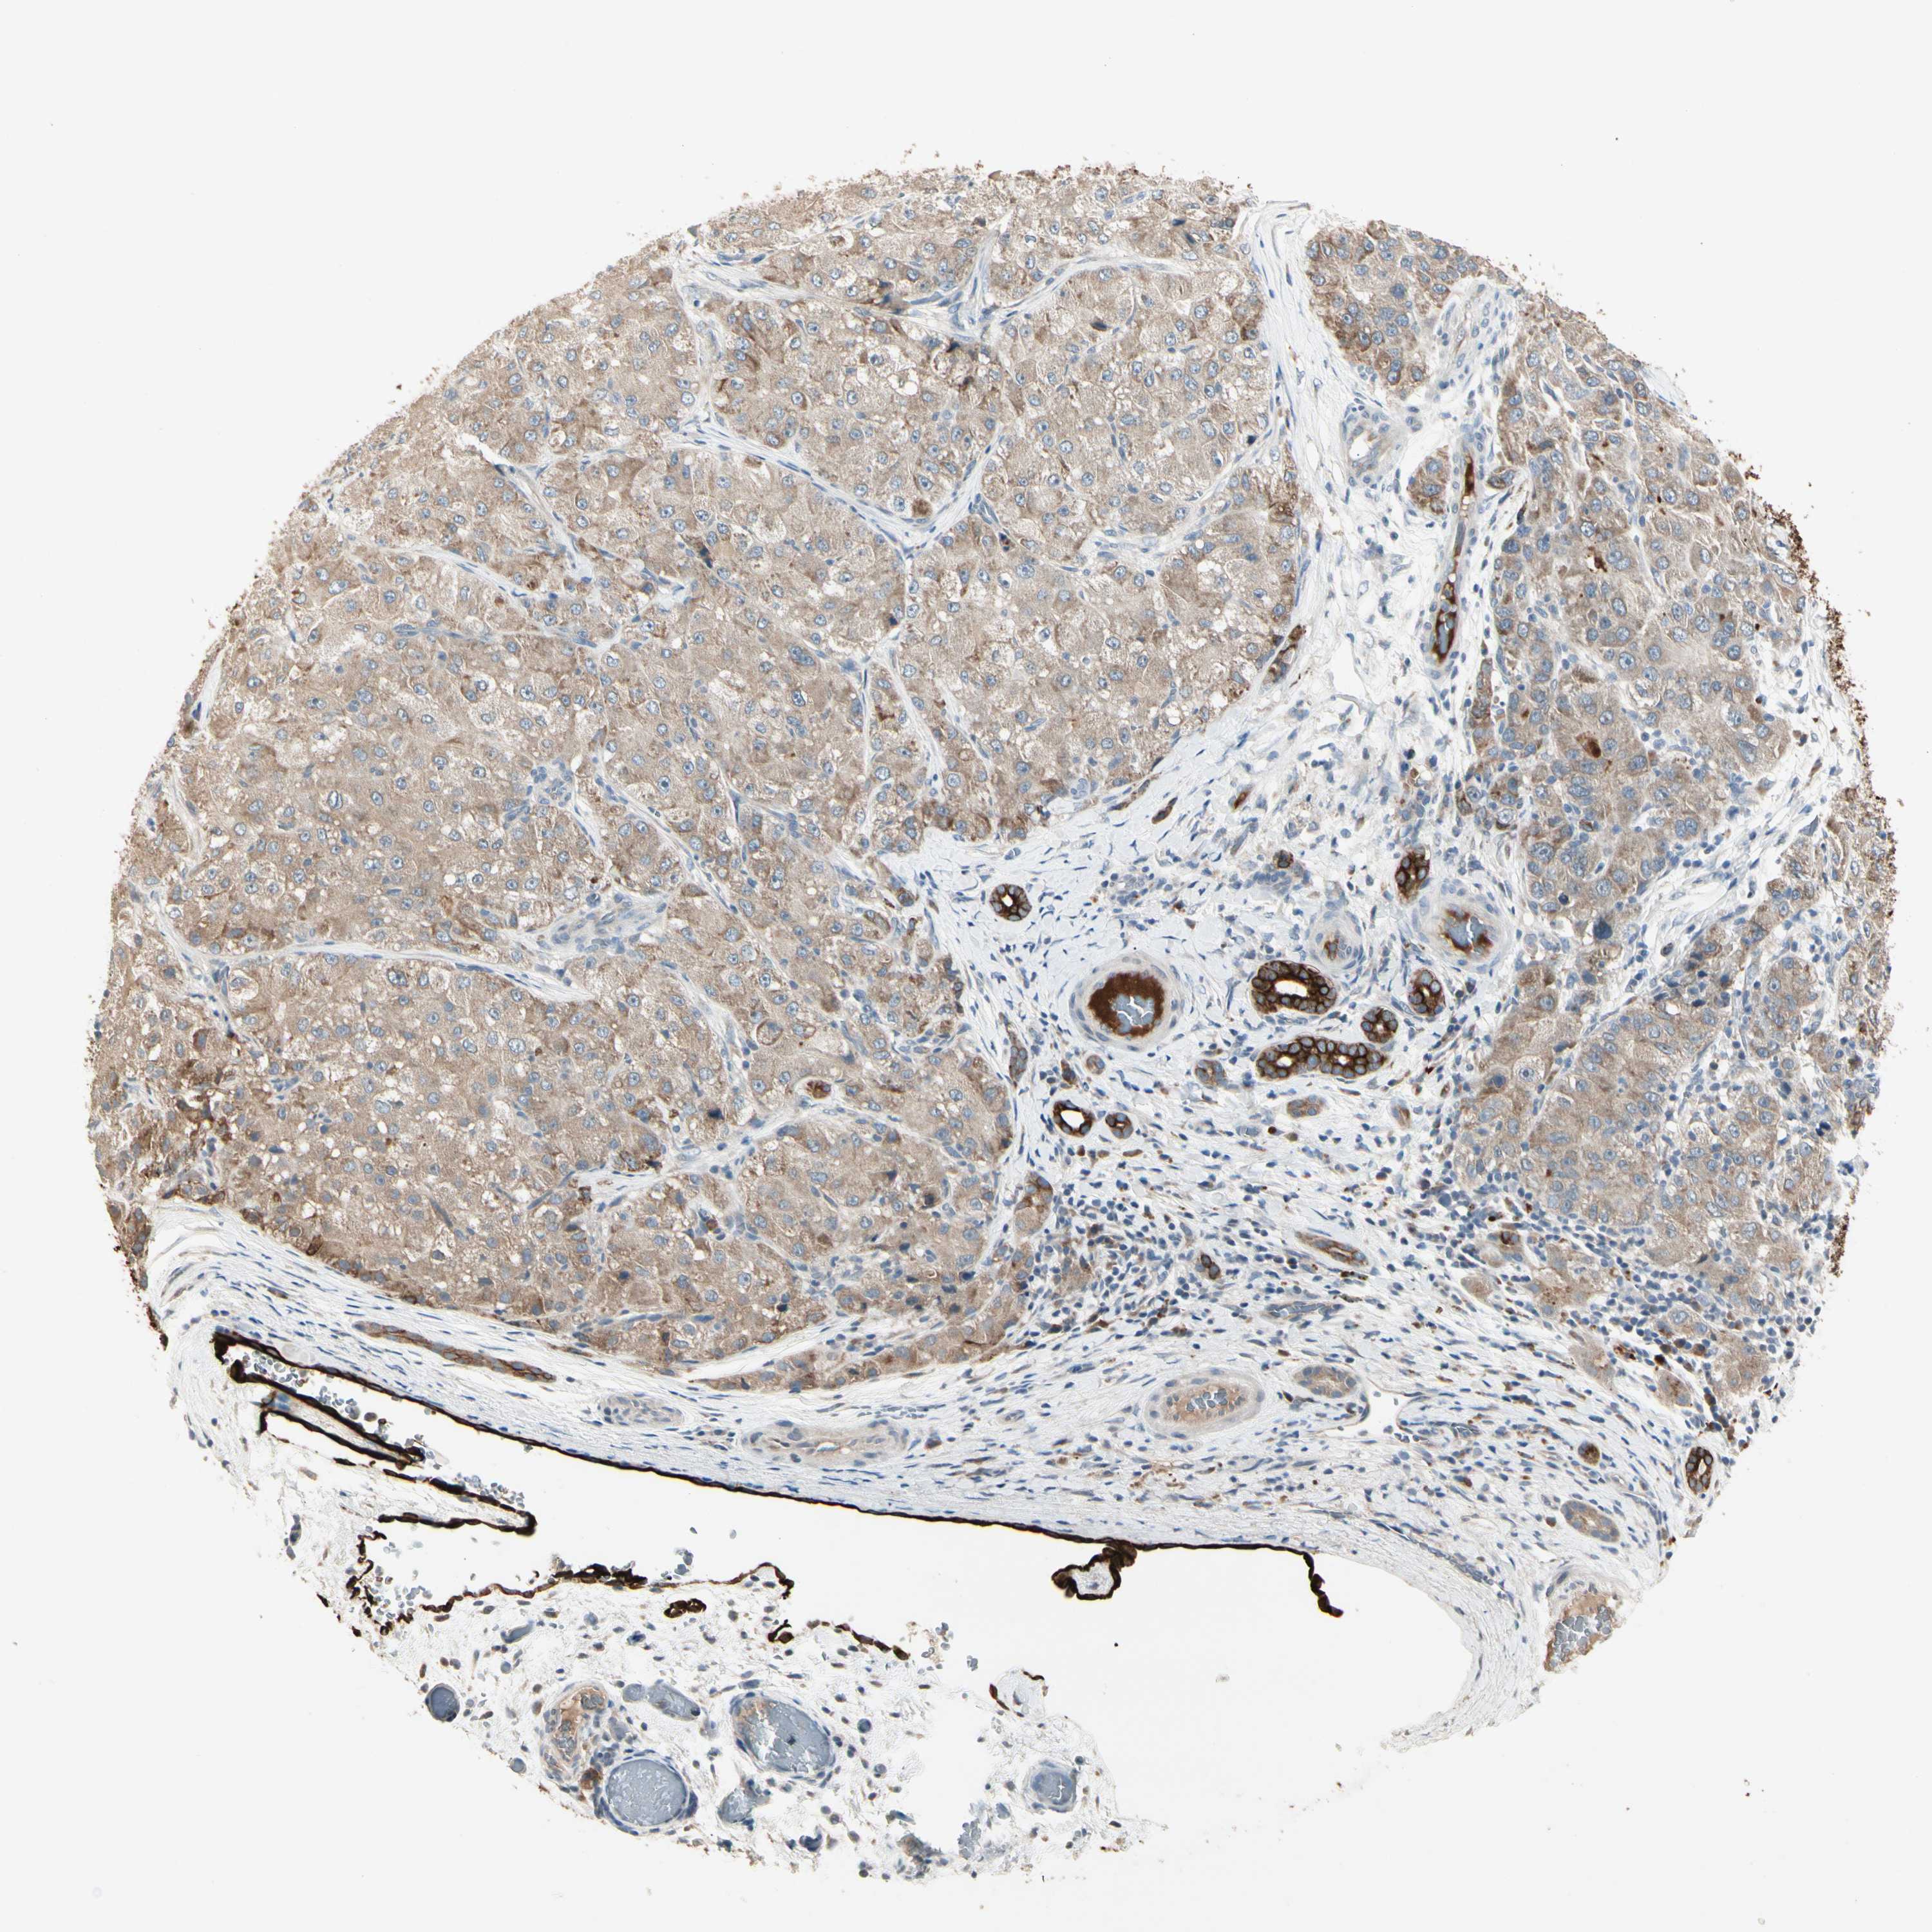

LIVER CANCER - Protein expressioni

A mouse-over function shows sample information and annotation data. Click on an image to view it in a full screen mode. Samples can be filtered based on level of antibody staining by selecting one or several of the following categories: high, medium, low and not detected. The assay and annotation is described here.

Note that samples used for immunohistochemistry by the Human Protein Atlas do not correspond to samples in the TCGA dataset.

Antibody stainingi

Antibody staining in the annotated cell types in the current human tissue is reported as not detected, low, medium, or high, based on conventional immunohistochemistry profiling in selected tissues. This score is based on the combination of the staining intensity and fraction of stained cells.

Each image is clickable and will lead to virtual microscopy that enables deeper exploration of all samples and also displays staining intensity scores, fraction scores and subcellular localization as well as patient and tissue information for each sample.

Antibody HPA008472

Staining

High

Medium

Low

Not detected

Intensity

Strong

Moderate

Weak

Negative

Quantity

>75%

75%-25%

<25%

None

Location

Nuclear

Cytoplasmic/membranous

Cytoplasmic/membranous,nuclear

Cholangiocarcinoma

Carcinoma, Hepatocellular, NOS